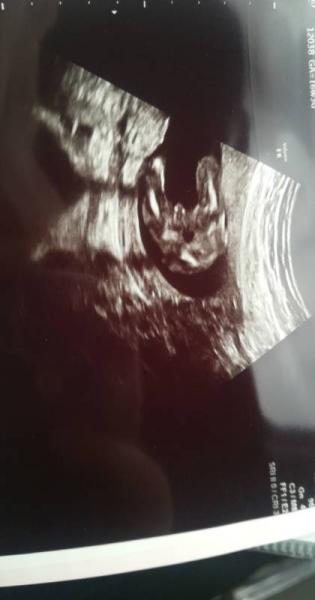

Also ich war gestern erst beim Arzt, bin auch in der 17 ssw und wir bekommen einen Buben das Bild ist glaube ich eindeutig genug

Bild zu